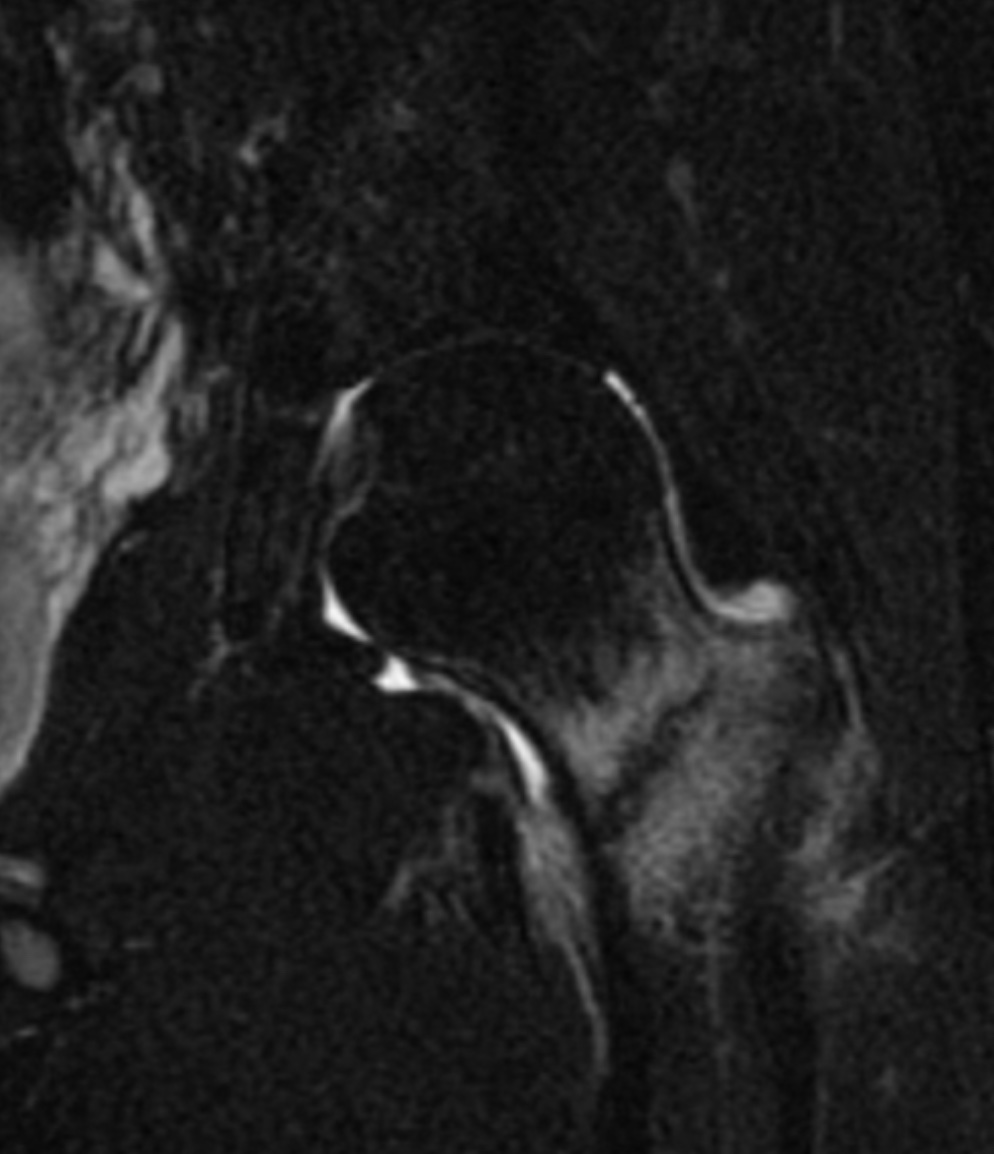

Figure A is an AP radiograph of a left hip demonstrating a sclerotic line along the inferior aspect of the base of the femoral neck, suggestive of a compression-sided femoral neck stress fracture. Illustration A is a T2-weighted MRI of the same patient, demonstrating a fracture line that spans greater than 50% of the femoral neck.

This young female patient has symptoms and radiographic findings consistent with a compression-sided femoral neck stress fracture. The next best step is an urgent MRI to determine the extent of femoral neck involvement (Answer 4).

Robertson and Wood provide a comprehensive review of femoral neck stress fractures in athletes. They note that while small compression-sided femoral neck stress fractures are at low risk of progression, those with greater than 50% involvement of the femoral neck have a high risk of progression and oftentimes require surgical intervention. They conclude that MRI is the study of choice to determine the pattern and extent of neck involvement.